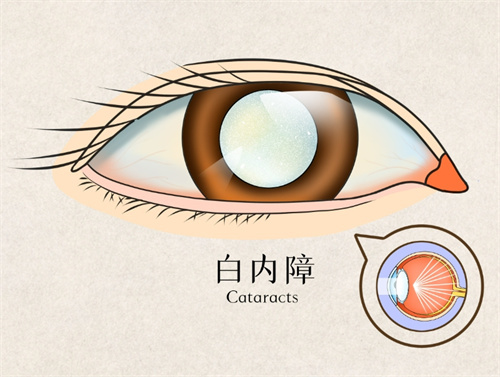

在眼科医疗领域,德国制造常被视为品质与技术的代名词。作为德国本土深耕眼科器械的品牌,德国人类光学(Human Optics)凭借其人工晶体产品,在白内障、老花眼等视力矫正领域占据重要地位。

其产品以“个性化适配+高性价比”为核心,覆盖单焦点、双焦点等类型,尤其适合高度近视、远视及复杂眼病患者。

适用人群:白内障合并老花眼患者,尤其适合需频繁切换视距的办公人群。